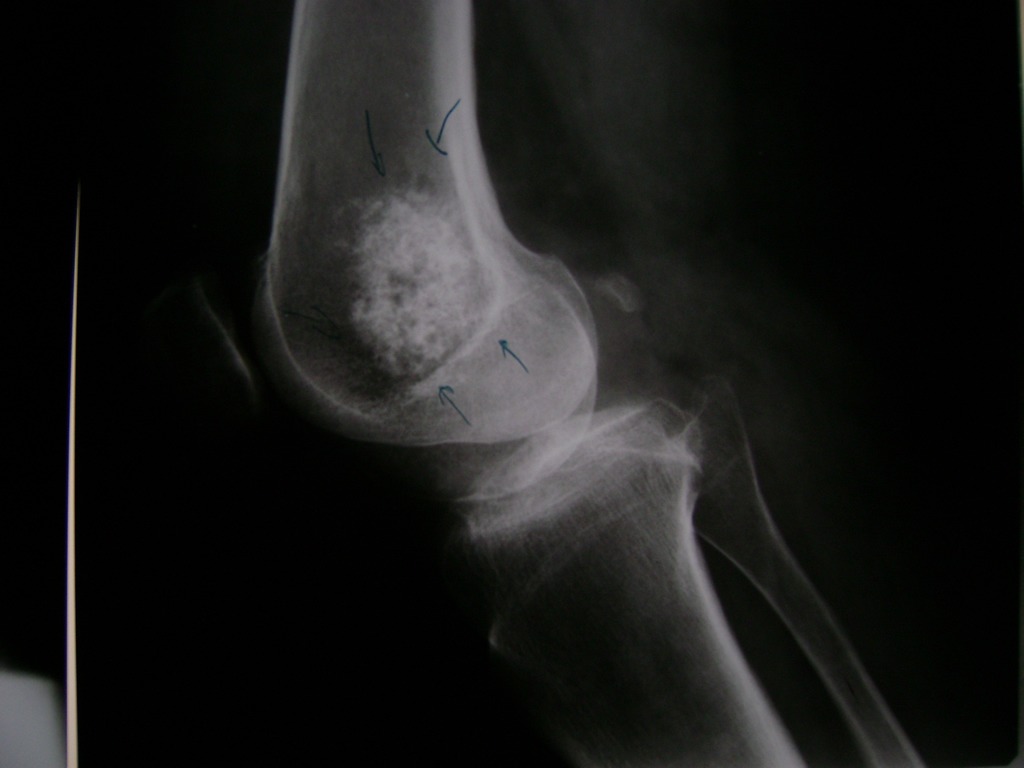

Fémur - Rodilla

La artroscopia de rodilla es un cirugía en el cual la estructura interna de la articulación es examinada ya sea para realizar un diagnostico o para realizar un tratamiento, este procedimiento se realiza utilizando un instrumento parecido a un pequeño tubo llamado artroscopio.